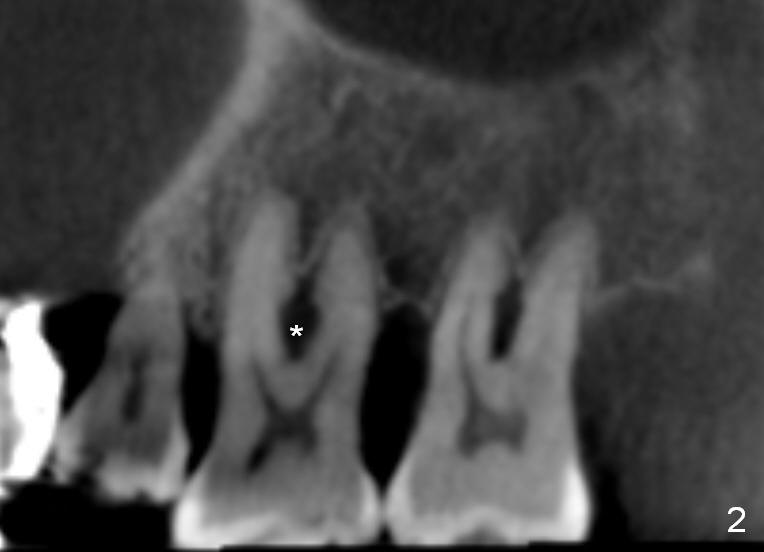

A 41-year-old man has chronic periodontits with bruxism. The teeth #14 and 15 are supraerupted (Fig.1 arrows) with furcal lesion (Fig.2 (CT) *). These 2 molars have guarded to poor prognosis. Due to insurance benefit limitation, we plan to save them temporarily with periodontal surgery so that bone loss would not get worse when the teeth are being intruded. After opposing implant placement (Fig.3), flaps are raised to remove calculus and granulation tissue (Fig.4, no bone graft). Twenty days later, three mini-implants are placed (Fig.5,6). The implant distopalatal to #15 is loose nearly 2 months postop (Fig.7 *) and retightened. The following month the same implant is placed higher for stability (Fig.8). The Intrusion takes <5.5 months (Fig.9,10).